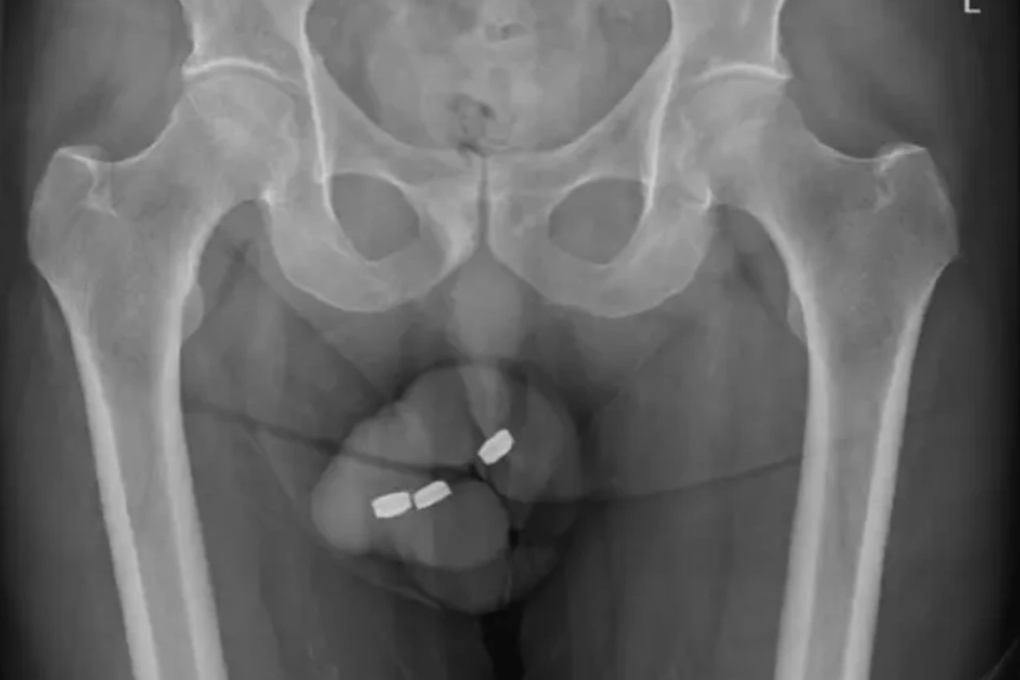

Hình ảnh chụp X-quang cho thấy 3 viên pin bị kẹt lại trong dương vật người đàn ông 73 tuổi (Ảnh: Ny Post).

Theo báo cáo, người đàn ông 73 tuổi ở Úc đã tự nhét ba viên pin vào niệu đạo của mình, nhưng sau đó không thể lấy chúng ra. Những viên pin này là loại pin cúc áo, có kích thước khoảng 1cm.

Khi nhìn vào ảnh X-quang của bệnh nhân nam này, các bác sĩ đã không khỏi bất ngờ khi phát hiện ra dị vật ở vị trí mà họ không ngờ đến. Người đàn ông đã chia sẻ với các bác sĩ rằng, ông nhét pin vào niệu đạo vì mục đích "tự thỏa mãn", và trước đây ông không gặp bất kỳ vấn đề nào với hành động này.